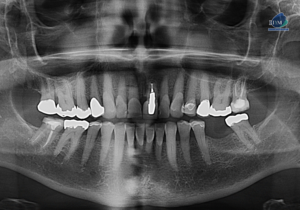

Paciente femenino de 16 años acude al Instituto de Diagnóstico Maxilofacial (sede Miraflores) para evaluación quirúrgica. Radiografia Panorámica A la evaluación de la radiografía panorámica